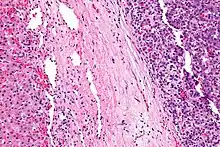

Micrograph of a hepatoblastoma. H&E stain.

Micrograph showing a hepatoblastoma (right of image) and normal liver (left of image). H&E stain.